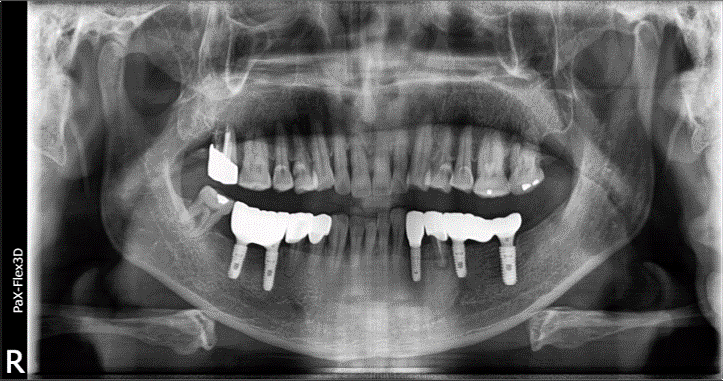

상기 환자분은 68세 남자분으로 임플란트 건강보험 적용 대상으로 본원에 치료를 위해 내원하셨습니다.

오른쪽 아래 어금니인 # 46, 47 어금니 2개 보험 임플란트 진행하셨고요. (사진상 왼쪽)

왼쪽 아래 치아도 상당 부분 상실하셨지만, 보철을 새로 해야 하는 상태셨기 때문에 다른 치아들까지 저희 병원에서 치료받으시기로 결정하셨습니다.

68세 남성

(전) 2021-11-05, (후) 2022-08-26

먼저 # 46, 47은 임플란트가 단단히 고정될 만큼 뼈가 충분해서 별도의 뼈이식 없이 치료를 도와드렸고요.

3개월 정도 임플란트 픽스처가 잘 고정되었는지 확인 후 최종 보철물을 올려 보험임플란트 시술을 마칠 수 있었습니다.

그리고 왼쪽 아래 비어있는 # 33 치아는 임플란트를 진행했고요. # 34 치아는 크라운을 씌워 정상적인 기능을 할 수 있도록 해드렸습니다.

또한 # 35, 37 치아에 임플란트를 식립하고, 가운데 # 36 치아 자리는 임플란트 폰틱(아래사진 참고)이라고 해서 브릿지처럼 중간을 연결하는 가짜 치아로 시술해 드렸습니다.

총 치료 기간은 약 9개월 정도가 소요되었고요.

전후 사진을 보시면 상당 부분 비어있던 공간에 치아가 생기면서 음식 섭취 등의 기능적인 측면뿐만 아니라 심미적인 측면에서도 훨씬 더 개선된 모습을 확인하실 수 있습니다. ^^

치료를 마치고 난 후 훨씬 더 건강하고 젊어 보이는 모습에 환자분뿐만 아니라 저희 치료진 모두가 만족도가 높았던 사례입니다.